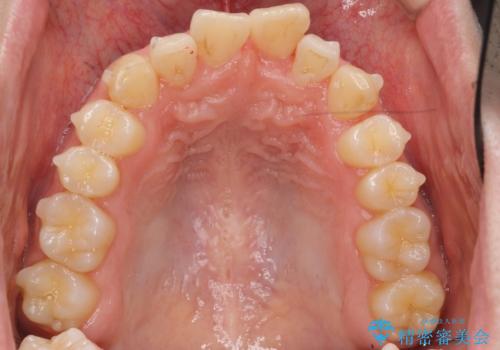

- 前歯のがたつきを主訴に来院。

左下の奥歯を後ろに移動して、中に入ってすれちがっていた小臼歯を並べました。

巷(ちまた)で大きく宣伝している某 格安マウスピース矯正では、奥歯を後ろに動かすことはできないです。

他院で歯を抜かずにマウスピースで難しいといわれた方、ぜひご相談ください。

奥歯を後ろに移動させるために、矯正用のミニスクリューを用いました。(インプラント矯正)